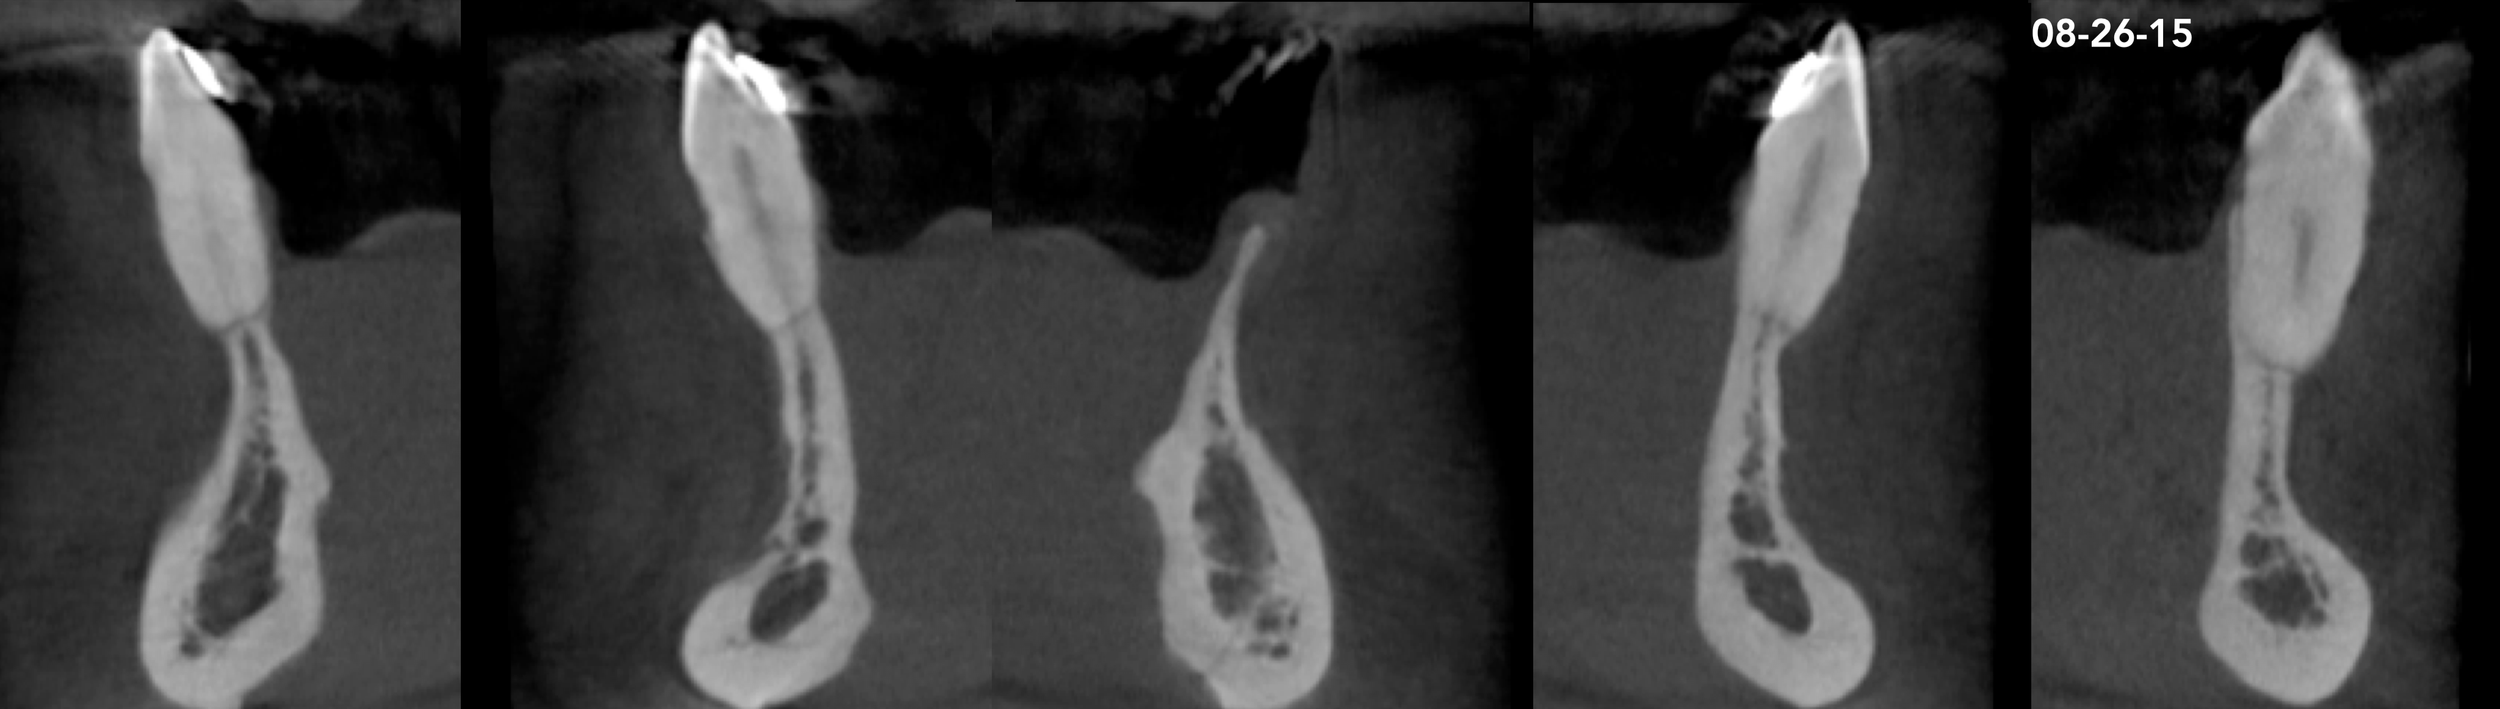

Clinical Cases CASE 1. COMPLEX IATROGENIC DEFECT CASE 2. CONGENITALLY MISSING LATERAL INCISORS CASE 3. VERTICAL AUGMENTATION CASE 4. VERTICAL AUGMENTATION CASE 5. IMPLANT BONE DEHISCENCE CASE 6. IMPLANT BONE DEHISCENCE CASE 7. KNIFE-EDGE RIDGE CASE 8. IMMEDIATE IMPLANT AND SIMULTANEOUS S.M.A.R.T.® HORIZONTAL AUGMENTATION CASE 9. IMMEDIATE IMPLANT AND SIMULTANEOUS S.M.A.R.T.® HORIZONTAL AUGMENTATION